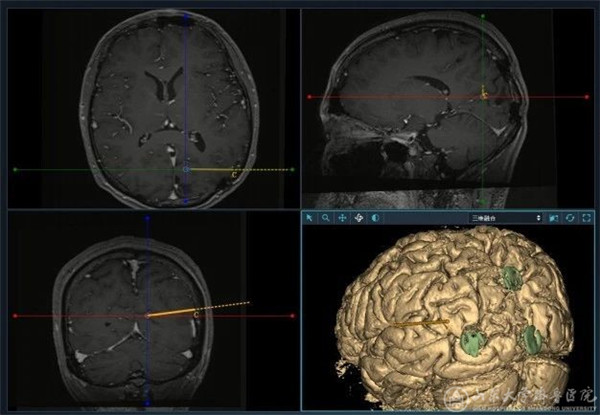

对药物难治性癫痫而言,如能够准确定位致痫灶并进行切除性手术,术后患者无发作率可达60-80%,因此术前评估一直是癫痫综合治疗的重点与难点。现阶段,对致痫灶的定位主要通过症状学、神经电生理、影像学及PET-CT等无创手段进行。如果上述手段无法准确致痫灶位置及范围,则有必要引入SEEG等有创诊疗技术。SEEG技术将定位手段从颅外引入颅内,从平面引向立体,可直接将电极放置至异常脑沟沟底、大脑内侧面、颅底、海马-杏仁核等常规皮层电极无法达到的部位,对大脑进行全方位立体化覆盖,从而准确定位病灶并判断致痫网络。在神经外科外科副主任、癫痫诊疗中心主任徐淑军教授带领下,癫痫诊疗中心外科团队先后完成了省内首例SEEG电极植入、机器人辅助SEEG植入及无框架SEEG 植入等手术,是目前省内完成SEEG手术台数最多,植入电极根数最多的单位,术后无颅内出血、感染等严重并发症,取得了良好的疗效及患者满意度。